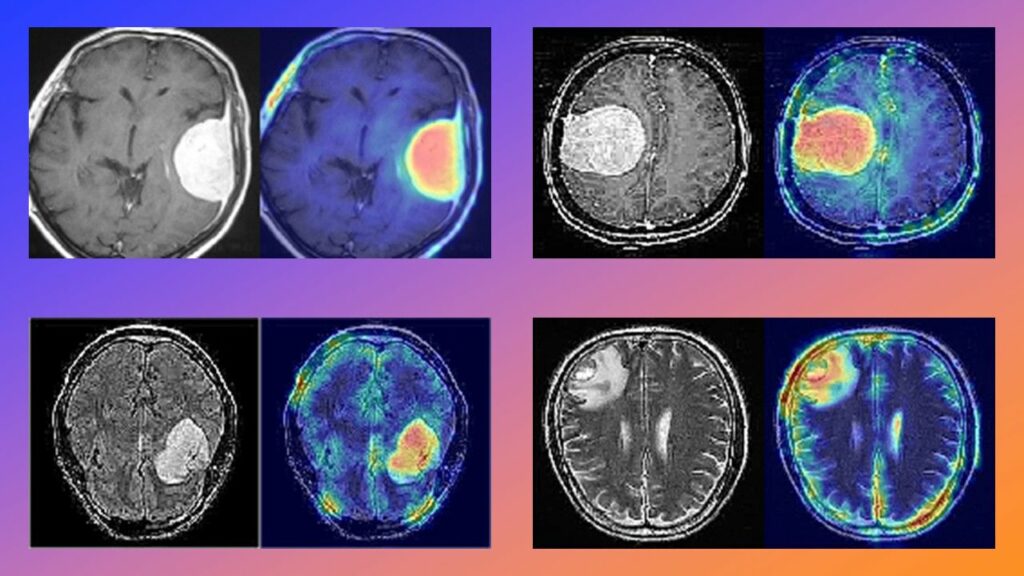

Abriendo la «Caja Negra» con Grad-CAM

Para responder a esto, implementé Grad-CAM (Gradient-weighted Class Activation Mapping). Esta técnica nos permite visualizar qué partes de la imagen original llevaron al modelo a tomar su decisión. Calculamos los gradientes de la puntuación de clasificación con respecto a los mapas de características convolucionales finales en el codificador.

Los resultados son sorprendentes. Los mapas de calor muestran claramente que el modelo se centra específicamente en la región del tumor para hacer su predicción, en lugar de basarse en artefactos de fondo o contornos del cráneo.

Pie de foto: Visualizaciones Grad-CAM. Las áreas «calientes» (rojo/amarillo) corresponden exactamente a la ubicación del tumor, validando la relevancia clínica del modelo.